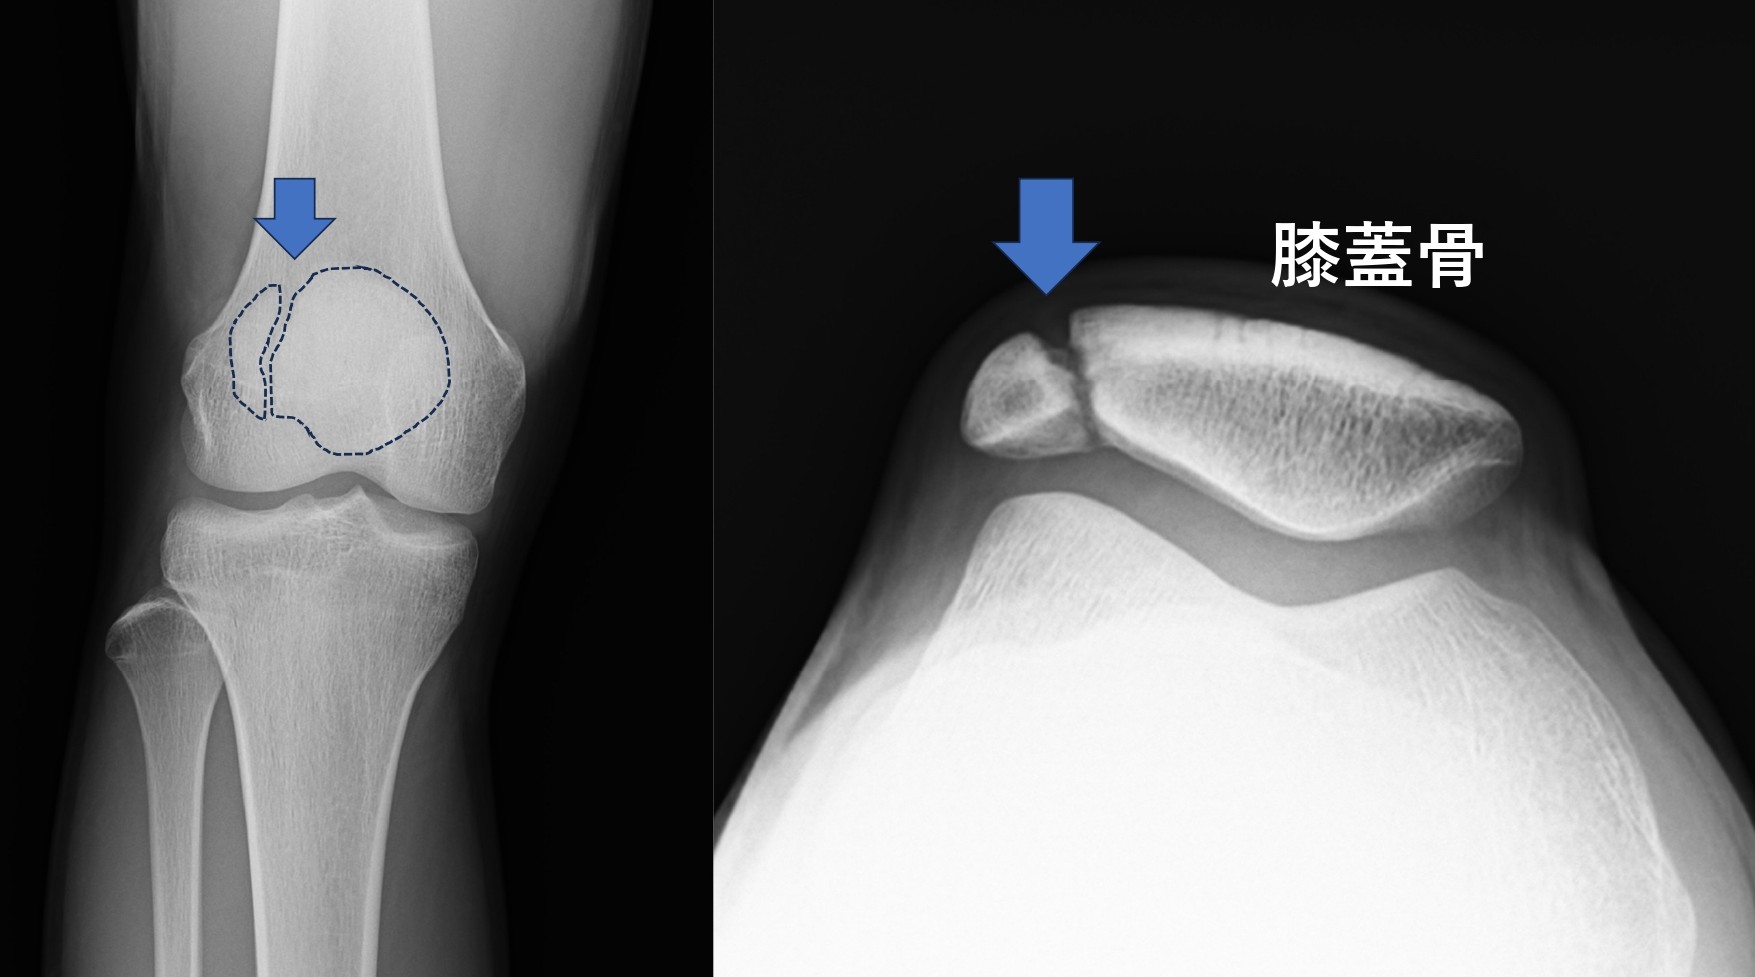

図1)14歳 男児 サッカー選手の右分裂膝蓋骨

膝蓋骨は、太ももの大腿四頭筋(だいたいしとうきん)という大きな筋肉の腱の中にあり、筋肉を効率よく働かせたり、腱の摩耗を減らしたり、関節を安定させたりと膝の重要な役割を担っています。一般的に「お皿の骨」と呼ばれ、2歳くらいから徐々に骨化がはじまります。膝蓋骨は一つの骨化中心から形成されますが、2割くらいのこどもには複数の骨化中心が存在していて、通常は複数の骨化中心が癒合して1つの膝蓋骨になるのですが、数%では癒合がおこらず、それぞれが独立した骨として成長し複数に分かれた膝蓋骨になることがあります。単純レントゲンやCT検査では、膝蓋骨が複数に分かれていて、境界部分がその名のとおり「分裂した」膝蓋骨となって確認されます。無症状であれば問題はありませんが、ジャンプやダッシュなどの繰り返し動作によって分裂部にストレスが生じると炎症が起こり、膝の痛みの原因となります。分裂膝蓋骨の発生形態によって3つのタイプに分かれますが、特に膝蓋骨の上外方にあるタイプは痛みが生じやすく、治療が必要になることがあります。